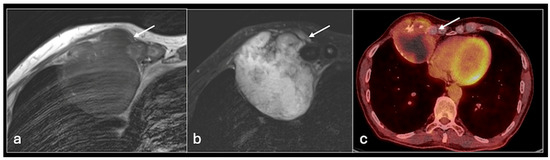

4.3. Ewing Sarcoma

- Plaza de Las Heras, I.; García Cañamaque, L.; Quílez Caballero, E.; Camacho-Arias, M.; Cárdenas Soriano, M.D.P.; Martel Villagrán, J. Positron emission tomography-magnetic resonance imaging applications in pediatric musculoskeletal tumors. Quant. Imaging Med. Surg. 2024, 14, 7825–7838. [Google Scholar] [CrossRef] [PubMed] [PubMed Central]